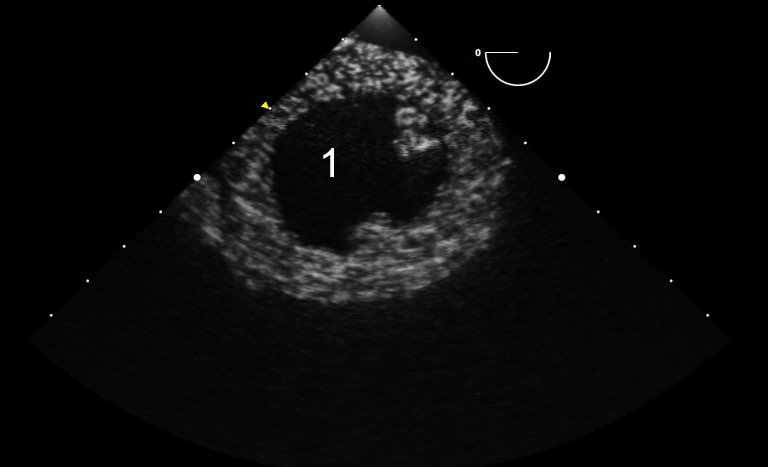

TEE Resus Transgastric Short Axis IU 2 Image

Left Ventricle